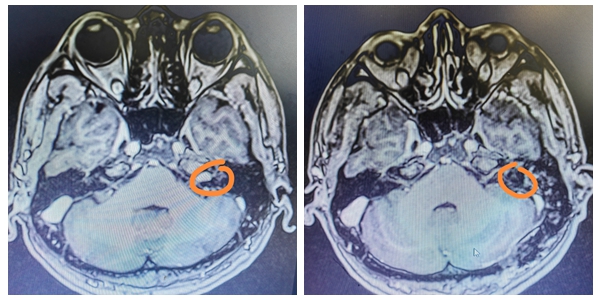

入院后,神经外科侯小飞主治医生接诊了丁先生,MRI检查发现,丁先生脑干旁有一0.7*1cm大小的肿瘤,考虑为:听神经瘤。对于听神经瘤,如何切除肿瘤后保留患者听力和面神经是一个世界性难题。能否成功施行这一手术,是考验一个神经外科医生的关键性指标。

手术前后对比图

术后,患者恢复良好,没有任何功能障碍,面神经功能得到保护,特别是听力得到恢复。丁先生苏醒后,发现自己听力强了很多,当时就高兴得眉开眼笑。